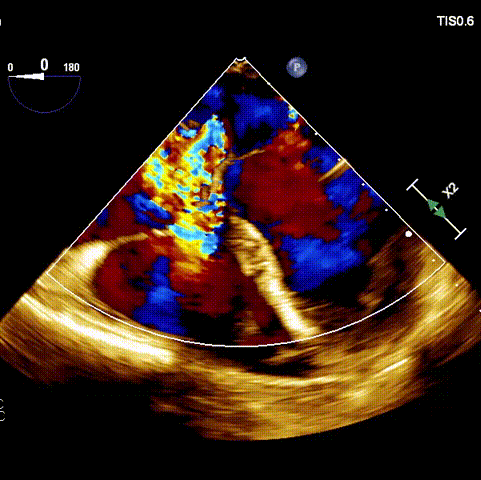

術(shù)前超聲

接受手術(shù)的為一名80歲男性,因“心悸2年,氣喘伴下肢水腫半年”入院。超聲心動(dòng)提示“極重度三尖瓣反流,右房及右室明顯擴(kuò)大,右心收縮功能輕度減低,左心收縮功能正常,肺動(dòng)脈壓力正常”。患者同時(shí)合并有“持續(xù)性房顫”及“慢性心力衰竭”,病史持續(xù)2年,規(guī)律口服抗凝及強(qiáng)心、利尿治療治療效果不佳,癥狀持續(xù)。經(jīng)廈心心臟團(tuán)隊(duì)評(píng)估后,認(rèn)為患者三尖瓣極重度反流并伴有心衰表現(xiàn),長(zhǎng)期內(nèi)科藥物治療效果不佳,且患者高齡、外科手術(shù)風(fēng)險(xiǎn)高,因此決定采用微創(chuàng)經(jīng)頸靜脈LuX-Valve Plus三尖瓣置換系統(tǒng)為患者治療。

術(shù)前經(jīng)過(guò)全面系統(tǒng)的評(píng)估后,考慮患者存在高齡、心功能減低、三尖瓣瓣環(huán)重度擴(kuò)張(三尖瓣極重度反流)等高危因素,因此廈心結(jié)構(gòu)心團(tuán)隊(duì)聯(lián)合超聲心動(dòng)、麻醉及護(hù)理團(tuán)隊(duì),制定了詳盡的圍術(shù)期治療方案及術(shù)中治療難點(diǎn)預(yù)案。術(shù)中,由王焱院長(zhǎng)主刀,在蘇茂龍主任超聲心動(dòng)團(tuán)隊(duì)的輔助,上海市第一人民醫(yī)院陸方林主任的協(xié)助下,僅用時(shí)30分鐘,即順利完成了三尖瓣原位置換的手術(shù)。術(shù)中患者血流動(dòng)力學(xué)穩(wěn)定,術(shù)后即刻顯示LuX-Valve Plus瓣膜位置良好,固定穩(wěn)定,瓣膜功能正常,無(wú)瓣周漏。